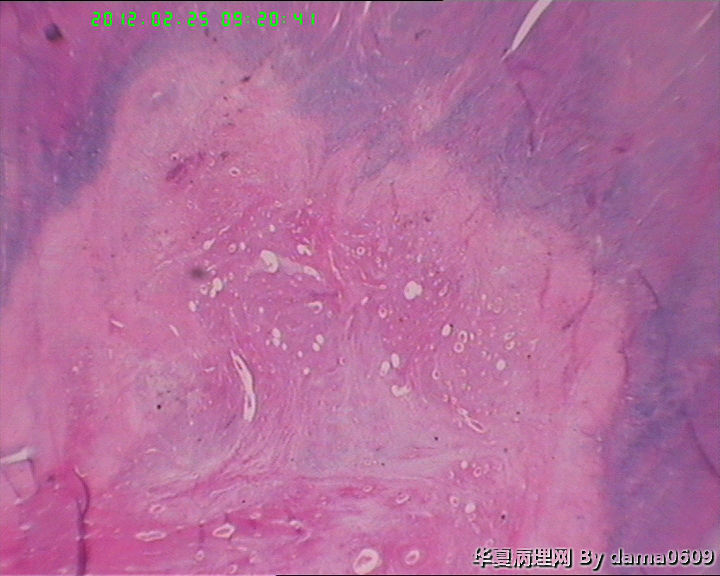

患者女性,48岁。临床未提供病史。

妇科以“子宫肌瘤”手术,术中子宫光滑、与周围无粘连。

追问患者家属病史,曾以药物治疗子宫肌瘤,具体情况不详。

巨检:次全切子宫,v:9.0x7.0x5.5cm,肌壁间见两枚肌瘤样结节,一直径0.6cm,无特殊;另一直径7.0cm,切面实性、质中、灰白、编织状、隆起、与周围肌层界限清。二者均呈典型平滑肌瘤外观。但体积大者,中心处局部见灰黄绿色坏死灶,直径约2.0cm,不规则,中间有点状红色区。

学生问题:1、这样的坏死在子宫平滑肌瘤中常见到,肉眼观界清,镜下坏死灶与周围正常组织陡然分界,无移行带,又不见明显炎细胞浸润,故怀疑是否为凝固性坏死??坏死灶内坏死平滑肌细胞无异形性,但轮廓清晰可辨,是否为“鬼影细胞”?

• 子宫肌瘤坏死,是何性质?!请指教!图1

图1